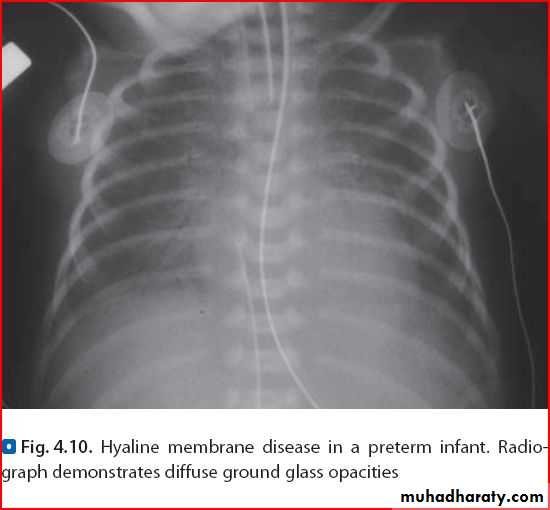

Normal xray after FB removalRds ( fine reticulo-granular pattern ) كعب البطل

Ground glass apperance